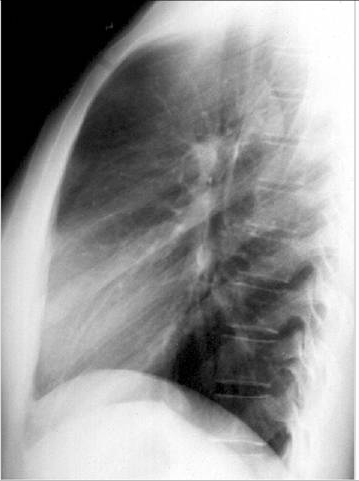

照片名称:右中叶肺不张(侧位)